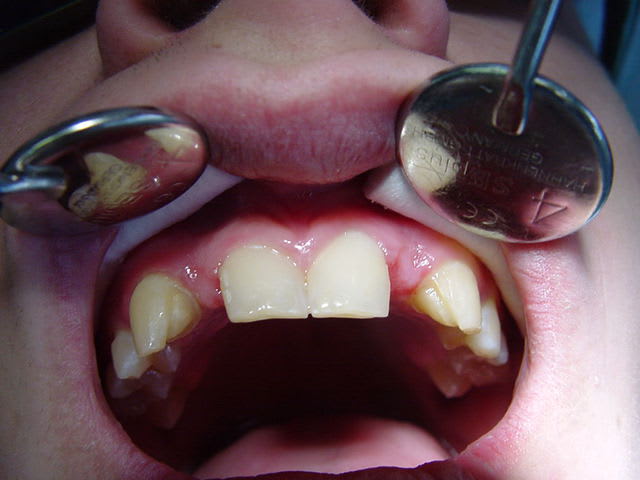

26/11/2010 à 22h47

préparations pour bridge collé ...des commentaires?

Dsc00088 s3ie5k - Eugenol

Dsc00092 jmfmzu - Eugenol

tu fais un léger retour vestibulaire en mésial des canines, tu ne crains pas que ça devienne visible?

sinon occlusion? et ça parait bien.

pas vraiment de retour mais je souhaitais modifier légèrement l'aspect morpho des canines,

l'occlusion était un peu serrée au niveau des centrales ,mais il y a agénésie des 41 et 31 et j'ai remodelé le bridge collée antagoniste provisoire.

La 13 semble avoir une limite trop vestibulaire en effet...faudra voir le collage final...